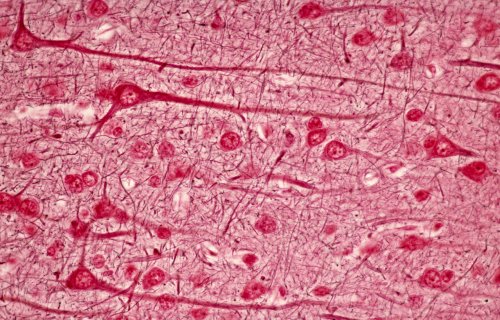

A high magnification of the cortex showing the cells of Retz (large pyramidal cells).

Fig 061-007 |